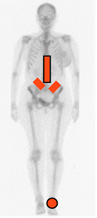

Produce artritis asimétrica en las extremidades inferiores, siendo el calcáneo el mas frecuentemente afectado. También aparece sacroileitis bilateral simétrica o asimétrica. (1). (Fig 55).

Fig 55. Distribución de la artropatía por síndrome de Reiter.

Compromiso dorsolumbar, de las sacroiliacas y del calcáneo.